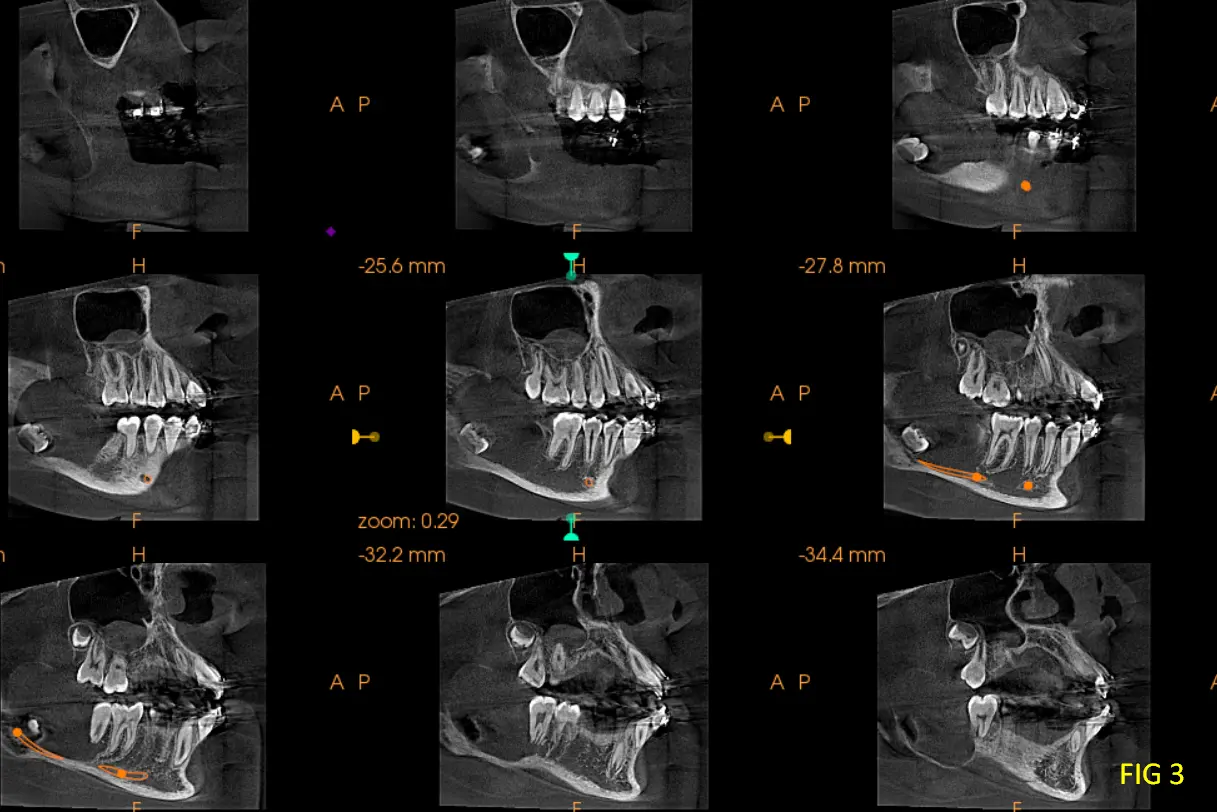

En las reconstrucciones 3D y cortes multiplanares (ver Fig 1, 2 y 3) se observa lesión hipodensa, unilocular, ubicado en rama mandibular, expandiéndose desde la rama ascendente mandibular hasta el ángulo y parte posterior del cuerpo mandibular, su contenido es homogéneo, involucra al germen de la pieza dentaria 48. Desplaza el conducto hasta la basilar, expande tabla lingual y vestibular.

En cortes coronales (Fig. 4) se aprecia los bordes definidos y parcialmente corticalizados que trata de delimitar la lesion, los cuales se encuentran sumamente adelgazados, como así también el desplazamiento de la hacia lingual pieza dentaria 47, y el desplazamiento de la pd 48 hacia la basal y hacia vestibular, los signos tomográficos nos llegavan a un diagnóstico presuntivo de Ameloblastoma Uniquístico. Se recomienda al profecional un estudio de Biopsia para tener un diagnóstico de certeza.